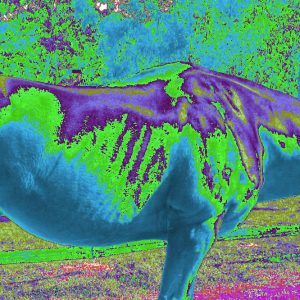

ERIC Works the Same with Animals: it can detect disease and problems with their health conditions

ERIC can detect injuries and sickness with horses.

Pictures show these horses have different body injuries and sickness.

Pictures show these horses have different body injuries and sickness.